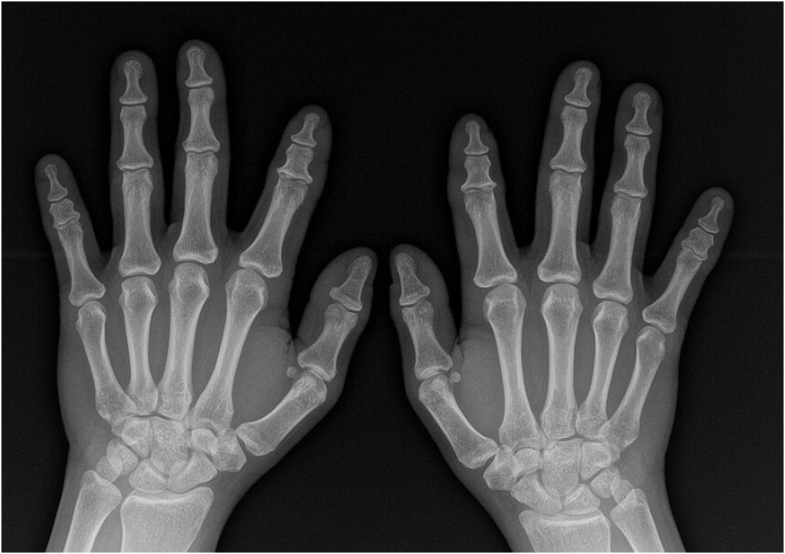

腕管综合征的手术减压通常是成功的,而失败是罕见的。持续性或复发性腕管综合征的诊断是基于彻底的记忆和临床检查,明确潜在的合并症,神经传导研究,并区分复发、持续或新发主诉。腕管释放失败的治疗可能需要翻修手术,包括腕横韧带的重新释放、外神经松解术和皮瓣。下鱼际脂肪垫皮瓣或其他局部、区域或远端皮瓣可用于重做腕管松解。目前,缺乏令人信服的证据证明附加皮瓣手术的优越性。术后护理正朝着早期运动而不是固定运动的方向发展,通过神经滑动练习来防止粘连并促进神经恢复。虚拟现实最近被添加到术后方案选择中。

Surgical decompression of carpal tunnel syndrome is usually successful, and failure is rare. Diagnosis of persistent or recurrent carpal tunnel syndrome is based on thorough anamnesis and clinical examination, defining underlying comorbidities, nerve conduction studies and distinguish recurrent, persistent or new complaints. Management of failed carpal tunnel release may require revision surgery, which includes redo release of the transversal carpal ligament, external neurolysis and flaps. A hypothenar fat pad flap or other local, regional or distant flaps may be added to a redo release of the carpal tunnel. Currently, convincing evidence to superiority of additional flap surgery is lacking. Postoperative care is evolving toward early motion rather than immobilization, with nerve gliding exercises to prevent adhesions and promote nerve recovery. Virtual reality was recently added to postoperative protocol options.